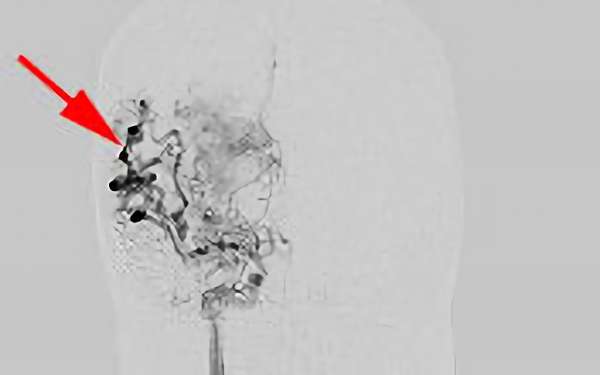

No.1620 手術後